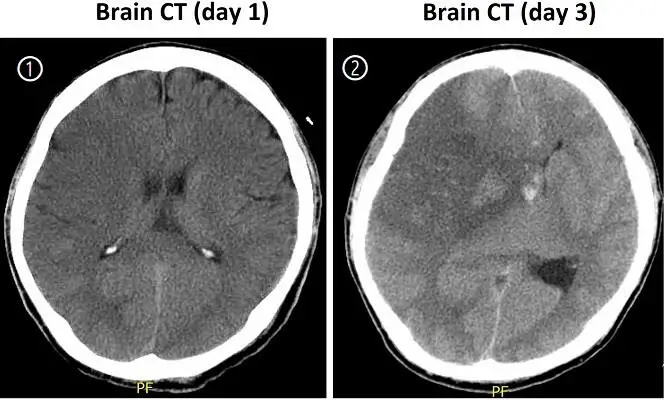

42歲男性病人突然發生左側肢體無力,無顯影劑之腦部電腦斷層( non-contrast CT )檢查結果如圖①,於 2天後病人因漸進性意識不清再次安排了腦部 CT檢查,結果如圖②。下列何種治療最有可能增進此病人的存活機會?

圖①(Day 1 non-contrast CT)

• 右側大腦半球(對應左側肢體無力)可見皮質下及深部白質輕度低密度(early ischemic change),並已有輕微腦溝鈍化與腦室輕度壓迫,顯示大範圍缺血性梗塞初期水腫。

圖②(Day 3 non-contrast CT)

• 右側半球廣泛低密度區域範圍擴大,伴重度腦溝消失、外側裂壓迫,中央裂及第三腦室受壓偏移約5–7 mm,並見部分出血性轉化的高密度斑點;這些變化已達「惡性MCA梗塞」影像標準,暗示顱內壓顯著升高且有腦疝高風險。